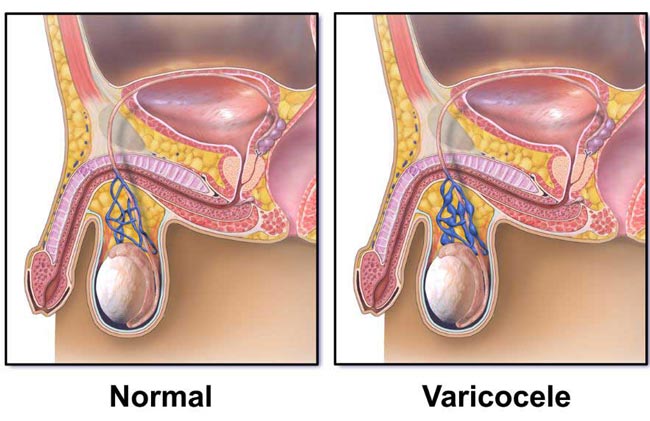

راه های درمان واریکوسل مردان

لازم نیست حتما واریکوسل را درمان کنیم اما در صورت بروز درد، ناباروری و یا آتروفی بیضه لازم است درمان واریکوسل را شروع کنیم. در حال حاضر توصیه می شود در صورت داشتن مواردی مانند واضح بودن وریدهای واریسی کیسه بیضه، کم شدن تعداد اسپرم و ناباروری دو ساله یا بیشتر و ناباروری غیر قابل توضیح بیمار تحت درمان قرار بگیرد.

در صورت نیاز به درمان تنها روش درمانی اصلی جراحی و یا کمک گرفتن از روشهای غیر جراحی تهاجمی است. هدف از جراحی این است که ورید آسیب دیده را خنثی کند تا جریان خون به وریدهای طبیعی منتقل شود. درمانهای اضافی مانند واریکوسلکتومی و آمبولیزاسیون واریکوسل ( مسدود نمودن عروق ) در صورت تشدید علایم ممکن است ضروری باشد. در ادامه به هر یک از انواع روش های جراحی واریکوسل جهت درمان میپردازیم.